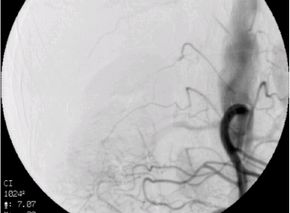

子宮筋腫に対する子宮動脈塞栓術(UAE)の実際

子宮動脈塞栓術(UAE)とは、子宮筋腫に栄養を与えている子宮動脈の血流を止めること

によって、筋腫を縮小させ、筋腫によって生じる過多月経などの症状を改善する治療法

です。足のつけ根に局所麻酔を行い、足のつけ根の動脈にカテーテルを入れ筋腫の近く

まで進めます。カテーテルから塞栓物質を注入し、血管を塞ぎ血流を止めます。塞栓が

完了したらカテーテルを抜き、傷口を押さえて止血します。

血管描出(塞栓前) 血管描出(塞栓後)